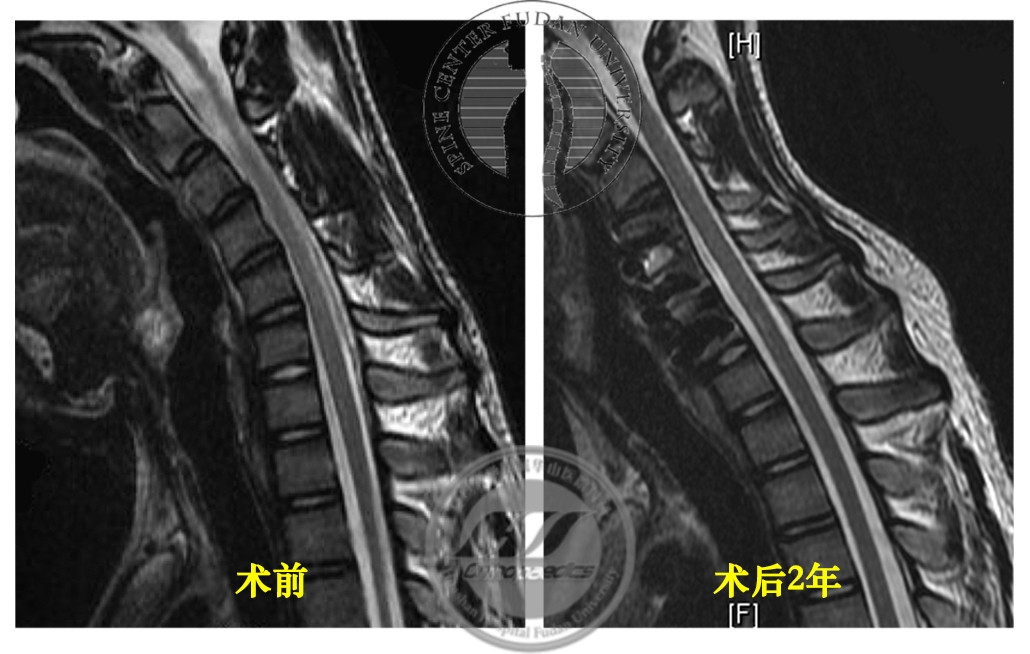

患者于2017年8月30日接受颈椎前路自体髂骨植骨融合内固定术,术后恢复良好,定期随访。最近一次随访为2019年9月(术后2年),患者诉右手握力较前增大,寒冷时症状较前好转,伸指震颤症状仍存在。X线示内固定无松动移位,屈颈位MRI显示“膜-壁分离”现象消失,屈颈位脊髓未见明显压迫,相邻节段未见明显退变(图6,7),神经电生理检查示所检肌自发电位消失,募集较前好转(图8)。

图7 术前与术后2年屈颈位MRI对比,术后T2加权像显示“膜-壁分离”现象消失